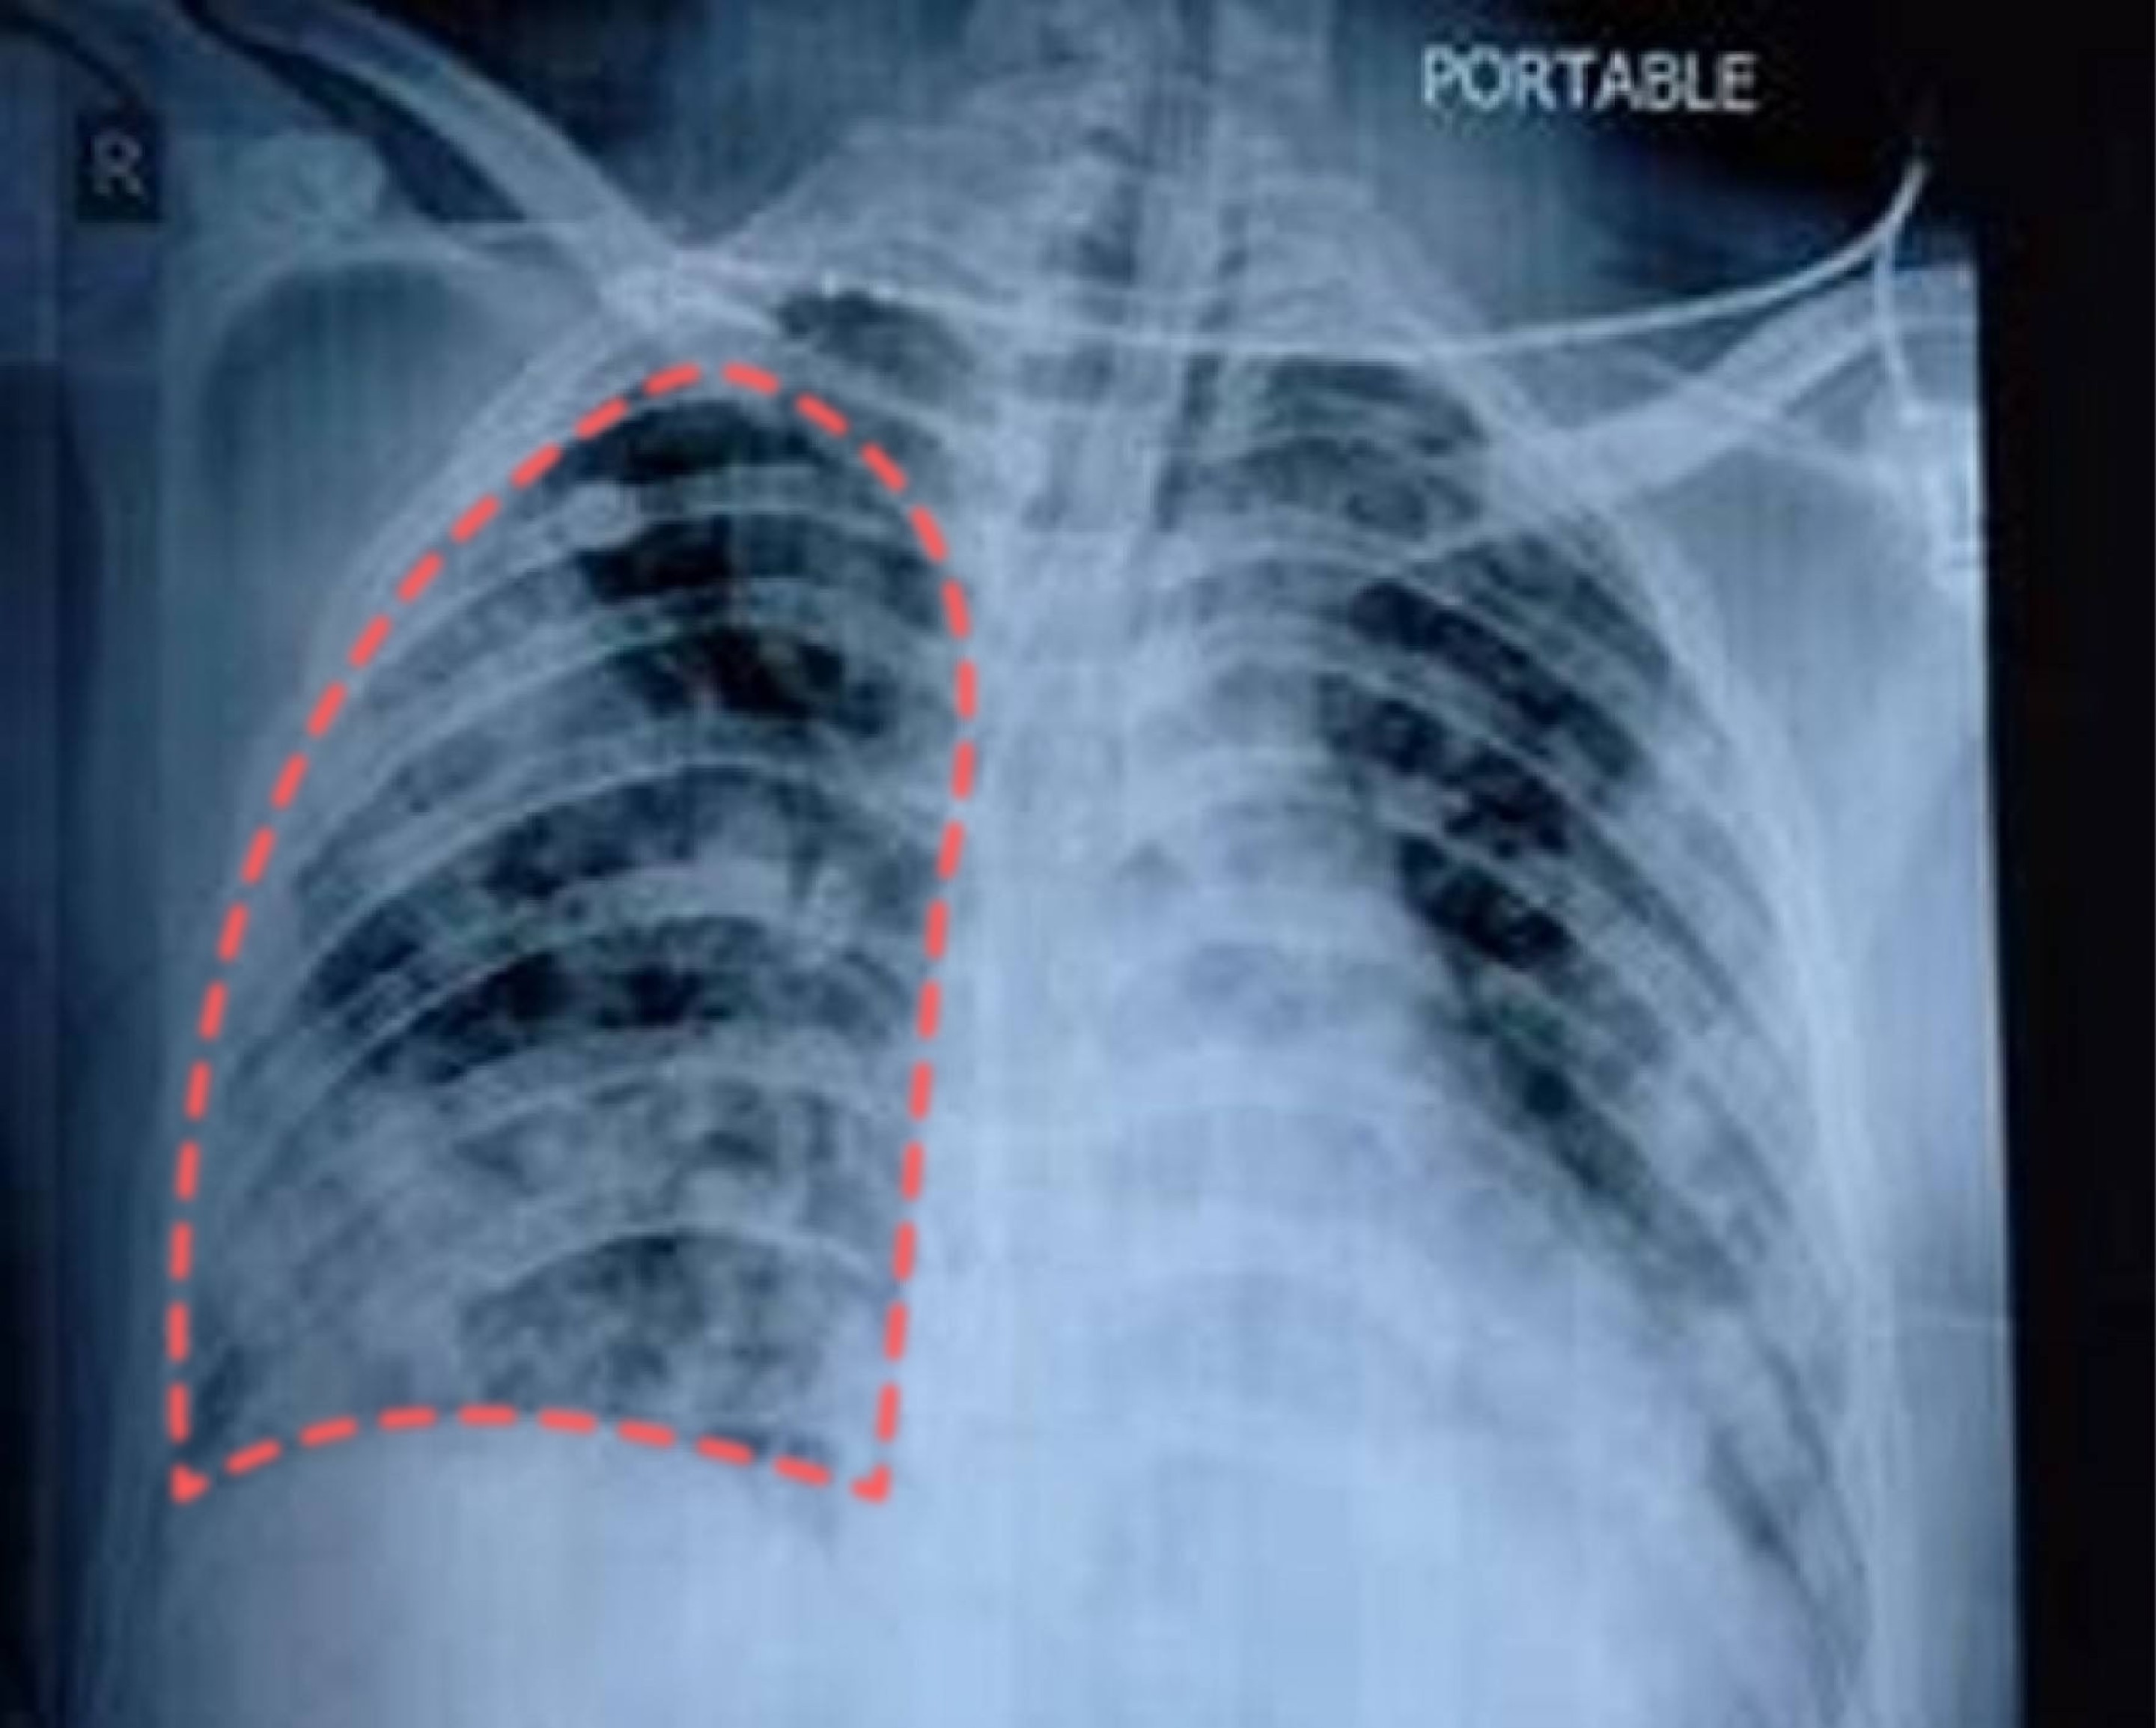

影像學檢查

| 胸部X光檢查 |

|

| 肺部電腦斷層掃描 (CT) |